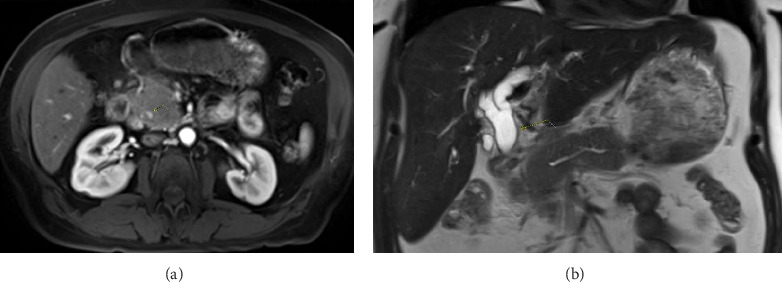

Introduction: Autoimmune pancreatitis (AIP) and pancreatic cancer are top differentials of obstructive jaundice originating from the pancreas. Case Description/Methods: The patient's findings were concerning for malignant biliary obstruction, but a thorough workup determined that the patient had AIP-NOS. She underwent EBS and was discharged on a steroid taper. Follow-up demonstrated complete resolution of symptoms, laboratory markers, and imaging. Conclusion: Adequate pancreatic tissue is not always obtained with 22-gauge needles. Biliary stenting is justifiable in AIP with significant hyperbilirubinemia. It is important to consider AIP for with a pancreatic head mass and obstructive jaundice to optimize outcome.

Abstract Image